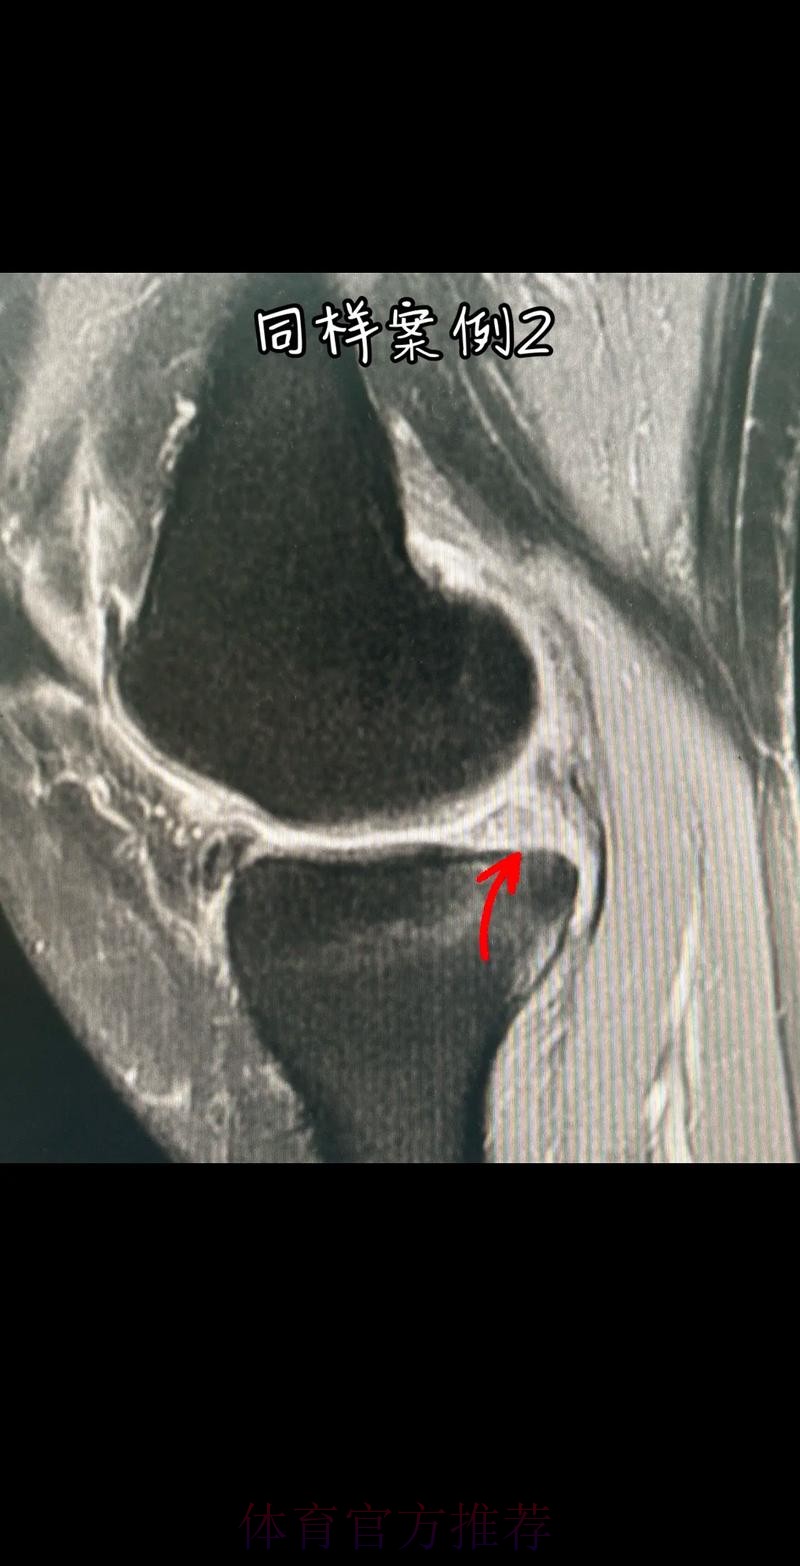

从医学角度看 半月板是膝关节内一块呈“C”形的软骨结构 其作用是缓冲冲击 稳定膝关节 并帮助分散压力 “左膝内侧半月板撕裂”通常说明在一次急停 旋转 或对抗中 半月板受到了超过其承受极限的力导致结构损伤 这类伤病常见于足球 篮球等需要频繁变向和对抗的项目 对于职业球员而言 半月板损伤严重程度不一 但共同点是都会影响支撑发力 跳跃以及变向时的稳定性 而官方给出的“预计伤缺6-8周”这个时间区间 往往对应的是中度损伤或通过微创手术加积极康复能够较快回归的情况 也意味着暂时没有出现必须长时间休战的最坏结果

表面上看 6-8周只是一个时间区间 但对顶级球队的赛程来说 这段时间可能包含多场联赛 甚至关键杯赛淘汰轮 相当于缺席一个赛季中最密集的一段周期 需要强调的是 这个“预计”并不是绝对数字 它取决于撕裂的位置 大小 修复方式 以及球员个体的恢复能力 有时若采取保守治疗 球员在6周时即可参与部分训练 但要达到比赛要求则可能接近8周甚至稍长 此外 精英运动员的康复不仅仅是伤口愈合 还包括力量恢复 协调重建 和心理自信的回归 阿拉巴要在有限时间内完成从“伤病患者”到“可靠首发”的角色转换 这一过程复杂程度远远超出一纸通告所能呈现